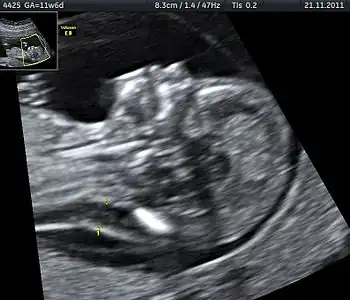

Ultrasound

Prenatal ultrasound can be used to screen for Down syndrome. Findings that indicate increased chances when seen at 14 to 24 weeks of gestation include a small or no nasal bone, large ventricles, nuchal fold thickness, and an abnormal right subclavian artery, among others.[113] The presence or absence of many markers is more accurate.[113] Increased fetal nuchal translucency (NT) indicates an increased possibility of Down syndrome picking up 75–80% of cases and being falsely positive in 6%.[114]

- Ultrasound of fetus with Down syndrome showing a large bladder